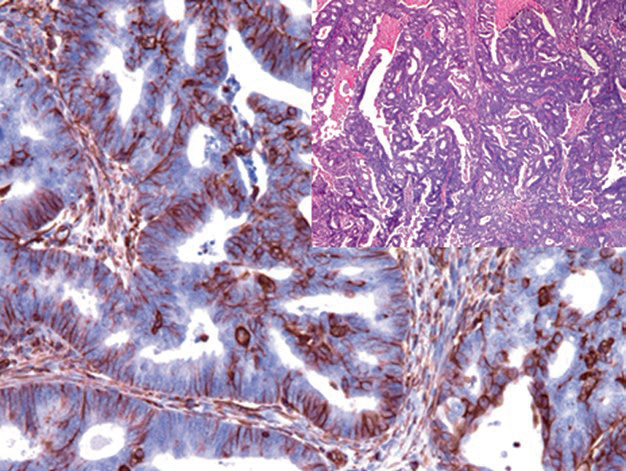

图1. 子宫内膜样癌中,肿瘤性腺体强阳性表达Vimentin。